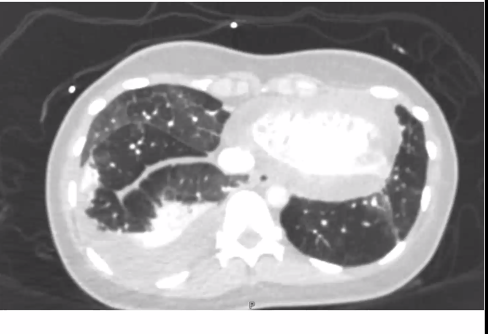

She goes to the ED and gets another CT... mosaicism is still there but now she has a new bilateral pleural effusions and interlobular septal thickening and atelectasis.

So both the plot, and the interlobular septa, have thickened.

Case is not over - but time to talk about PVOD!